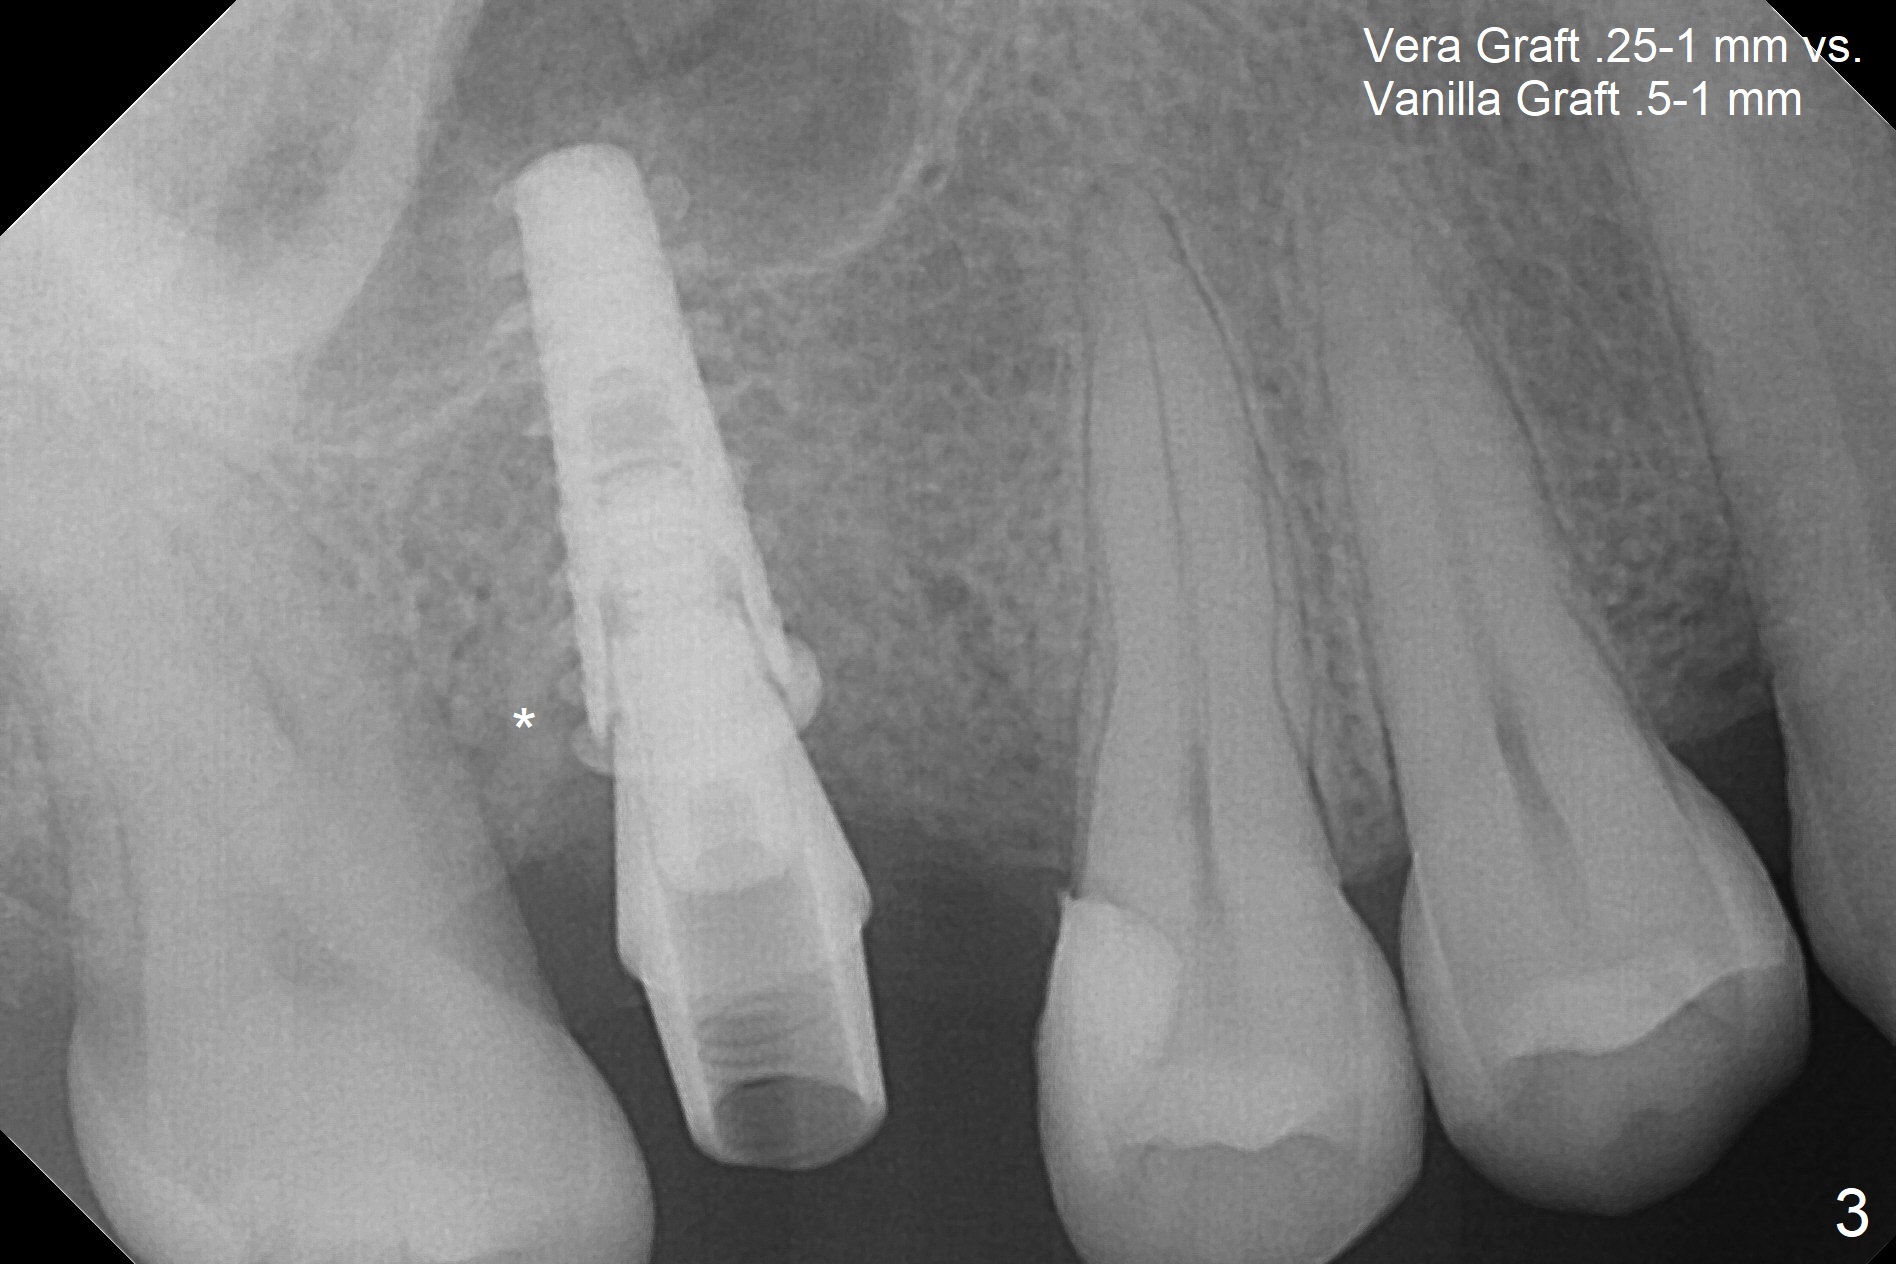

There are 2 sockets at #3 when the residual roots are extracted; osteotomy is established in the palatal one for 11 mm (gingival level; Fig.1), ~ 2 mm from the sinus floor (red dashed line). Following the last drill (3.8 mm) for 11 mm, a 4.5x11 mm dummy implant is placed 2 mm subgingival (Fig.2). In fact the sinus lift (red dashed line) is done by implant insertion, since the bone plug after Magic Drill is present in the apical portion of the osteotomy when the last drill is finished prior to implant placement.. After the dummy implant is removed, the definitive one (the same size) is placed with >50 Ncm, followed by placement of a 4.5x4(3) mm abutment and VeraGraft mixed with autogenous one (Fig.3 *). The most coronal portion of the socket is sealed with collagen plug. The latter is fixed in place by an immediate provisional. The mesial surface of the tooth #2 is reduced (Fig.4 <) prior to provisional fabrication. The implant is placed distal, which could be corrected by pushing the 2nd molar distal orthodontically. There is mild crestal bone loss nearly 8 months postop (Fig.5). An angled abutment (5x15 degrees, 3 mm cuff) is used before impression. CT is taken immediately post cementation (Fig.6 (8.5 months postop)). CT taken 8 months post cementation shows that the 4.5x11 mm implant barely passes the sinus floor (Fig.7). Return to Upper Molar Immediate Implant, Prevent Molar Periimplantitis (Protocols, Table), IBS, 30 19 Xin Wei, DDS, PhD, MS 1st edition 09/13/2017, last revision 01/31/2019